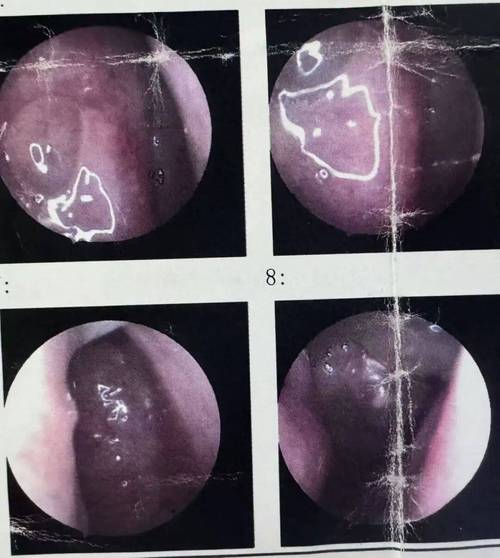

据悉,这位男士多年来的鼻窦炎症状反复发作,鼻塞、流涕和面部疼痛成为他生活中的常态,经过多次检查和药物治疗,病情始终未见明显改善,直到最近,在一次全面的鼻部检查中,医生意外发现其鼻腔内有一异物。

经过细致的手术操作,医生成功从患者鼻腔中取出了一根长达3厘米的树枝,经过分析,这根树枝可能是多年前患者不慎吸入鼻腔的,随着时间的推移,树枝在鼻腔内并未被自然排出,而是引发了长期的炎症和感染,导致鼻窦炎症状反复发作。